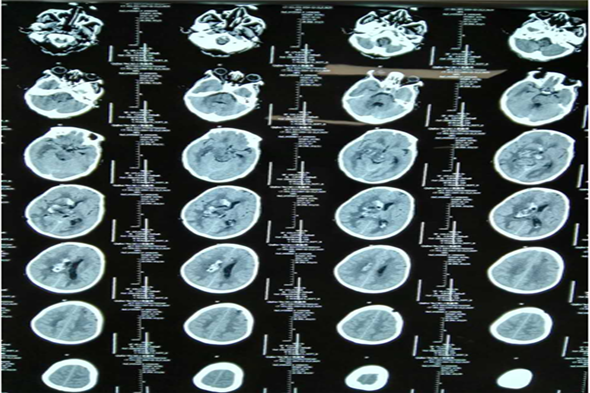

病例二 孙某,女,63岁,脑出血、脑疝。

术前脑CT

术后第三天脑CT

术后一周脑CT